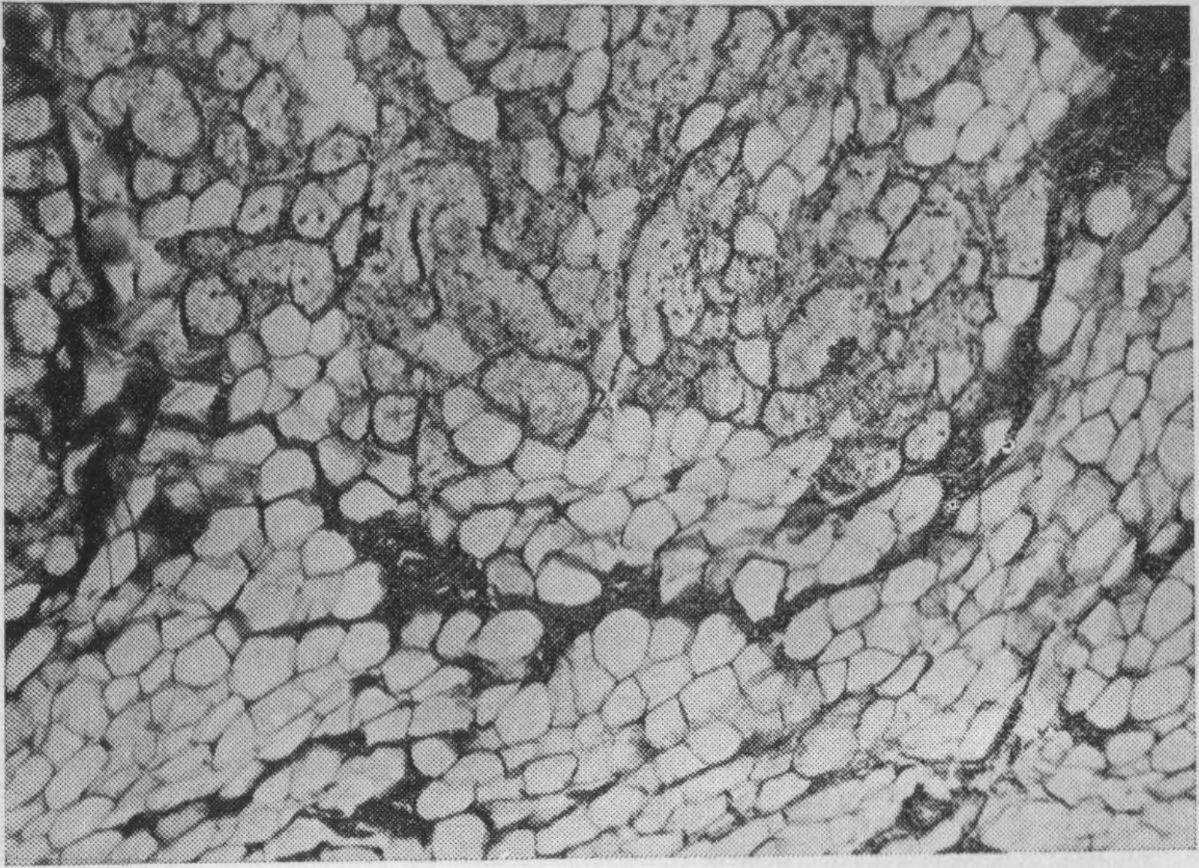

Рис. 44. Истончение надкостницы кости твердого неба.

Мужчина 65 лет, срок пользования протезом G лет. Окраска гематоксилинэозином. Х56 (Дуйшалиев К. Д.).

При увеличении сроков пользования протезами (более 3 лет) надкостница альвеолярного отростка и твердого неба заметно истончается (рис. 44), представляя собой плотную фиброзную ткань. Количество остеобластов

уменьшается. При большем сроке пользования протезами (более 8 лет) количество остеобластов в камбиальном слое уменьшается.

Таким образом, морфологические исследования показали, что ткани протезного ложа беззубой верхней челюсти отвечают определенной реакцией на те необычные условия, в которых они оказываются под базисом пластиночного протеза. При пользовании протезами до 3 лет надкостница альвеолярного отростка утолщается. Но с увеличением сроков пользования протезами она, наоборот, истончается, превращаясь в плотный слой фиброзной ткани. Остеобласты камбиального слоя исчезают. В кости твердого неба и альвеолярного отростка после 3-летнего пользования протезами отмечается выраженная резорбция за счет остеокластов, дистрофические изменения и понижение регенераторной потенции кости. Костные балки значительно истончаются, обычная архитектоника нарушается. Костномозговые полости заметно расширяются. Костный мозг замещается жировой и фиброзной тканью. Определенные морфологические изменения претерпевают также сосуды и нервы слизистой оболочки, надкостницы и костного мозга.